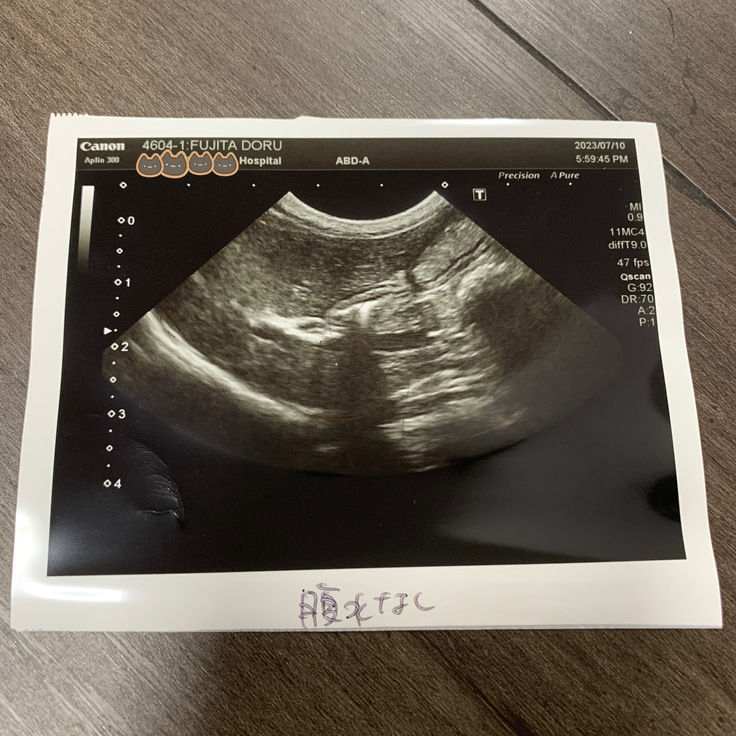

7/10はじめての検査.2

写真の掲載に失敗していました。

7/10 エコー写真

※腹水が完全に抜けました。